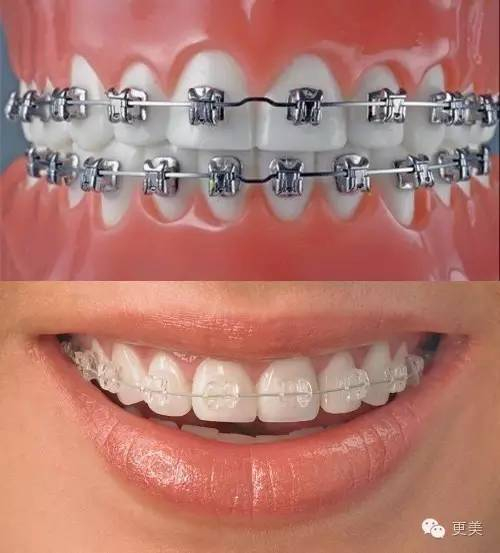

牙性的可以做正畸就不具体说了,可以选择的矫正器有很多种,金属的、陶瓷的、隐形的都有(具体了解如何选择牙套戳这里)

根据不同程度的问题,矫正时间几个月到几年的都有,并且校正后需要佩戴保持器,保持新的牙齿位置,等待牙槽骨改建,医生一般要求佩戴时间越长越好(成年矫正者需3-5年不等)

保持器佩戴时间:矫正后3-6个月内每天佩戴(20小时以上),3-6个月后每天晚上佩戴(10-12小时左右)